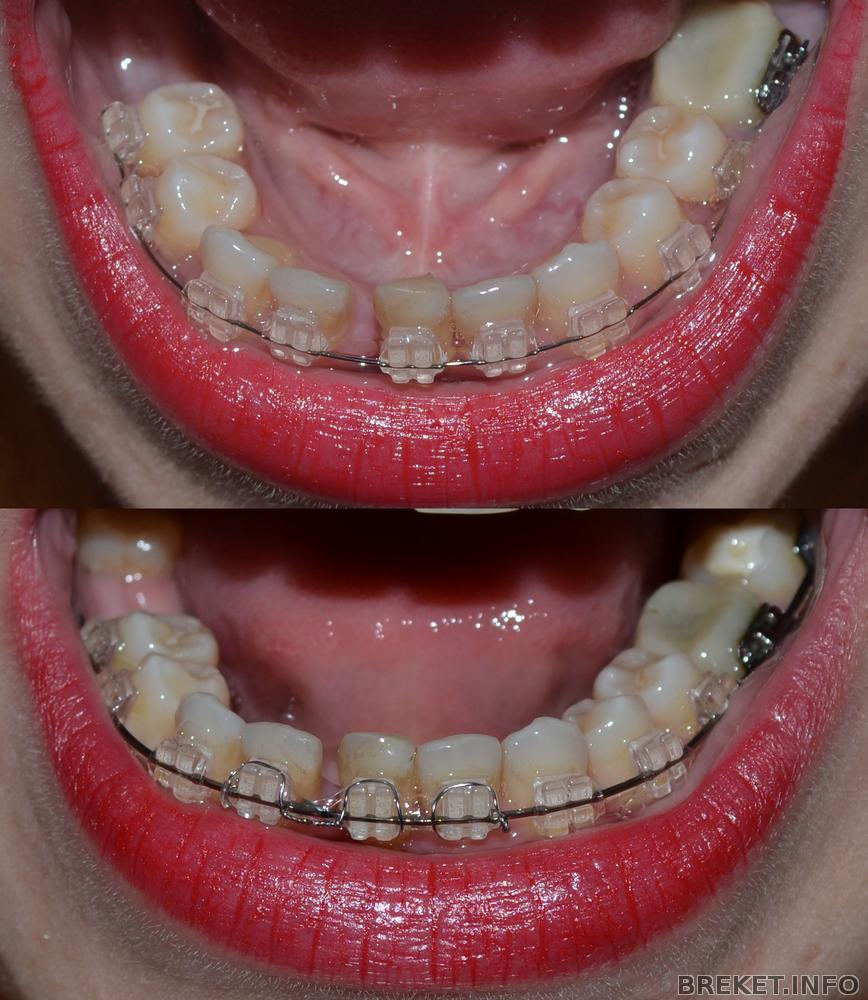

Сегодня ездила к орте. Спросила, когда же мы промежуток будем закрывать от удаленной единицы, она сказала, что промежутки закрываются на последних дугах. А потом подумала и сказала, ну ладно, чего мелочиться и поставила мне прямоугольную дугу на НЧ, накрутила чейн на 3 оставшихся резца и на них же повесила металлические лигатуры. Во как ![]()

Особо делиться нечем, прогресса уже нет, только появилась щель между клыком и четверкой на НЧ справа (на фото слева). Это упавший зуб приподнялся

Фотки все равно выкладываю для истории.